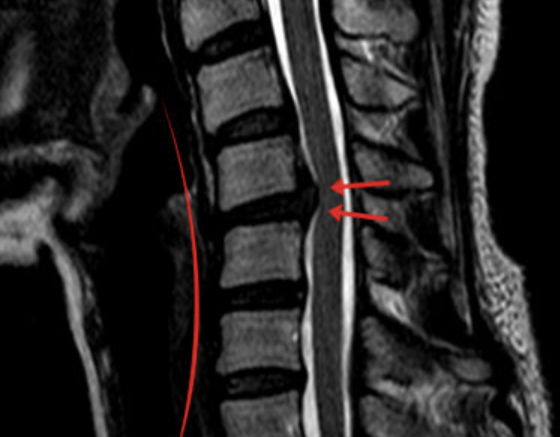

진단

▶ X-ray와 근전도 검사로 초기 확인이 가능합니다.

▶ 정확한 진단을 위해서는 MRI 검사가 필요합니다.